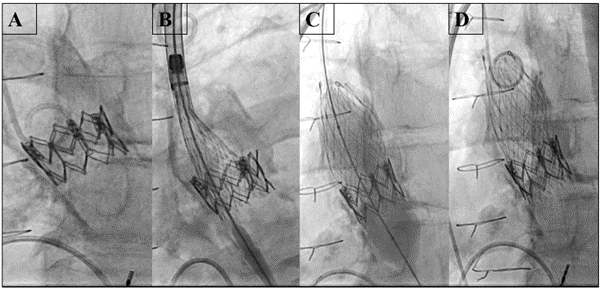

After pre-dilation with a 21-mm True balloon (BD), a 23-mm Evolut FX valve was deployed inside the original Sapien XT (Figure 2, Video 2) and post-dilated with the same balloon. Echocardiogram showed no significant transvalvular or paravalvular regurgitation and a mean gradient of 9 mm Hg (Video 3). At the 8-week follow-up, the patient reported significantly improved exercise tolerance, the transvalvular gradient was stable, and the LVEF improved from 25% to 42%.